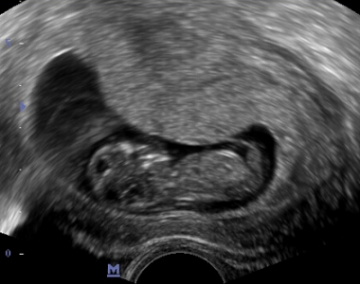

Celé těhotenství probíhalo v pořádku, první screening, test na cukrovku.. až se přiblížil 20tt a s ním druhý velký ultrazvuk. Byla jsem strašně nervózní a bála jsem se. Přijeli jsme do olomoucké fakultní nemocnice a čekali, až na nás přijde řada. Potom jsem skoro ani nebyla schopna dojít do ordinace. Při ultrazvuku jsem se paní doktorky pořád ptala na všechno možné, a když řekla, že je miminko v pořádku, začaly mi téct slzy štěstí. Mimo jiné jsme se dozvěděli, že opět čekáme chlapečka. Byl to nádherný pocit vědět, že je ten tvoreček uvnitř v pořádku a že má všechno, co má mít… Cestou zpět jsme začali přemýšlet nad jménem pro naše miminko, jména, která jsme měli vybraná pro Andílka, jsme už dát nechtěli, tak jsem nakonec rozhodnutí nechala na manželovi a ten vybral moc dobře.